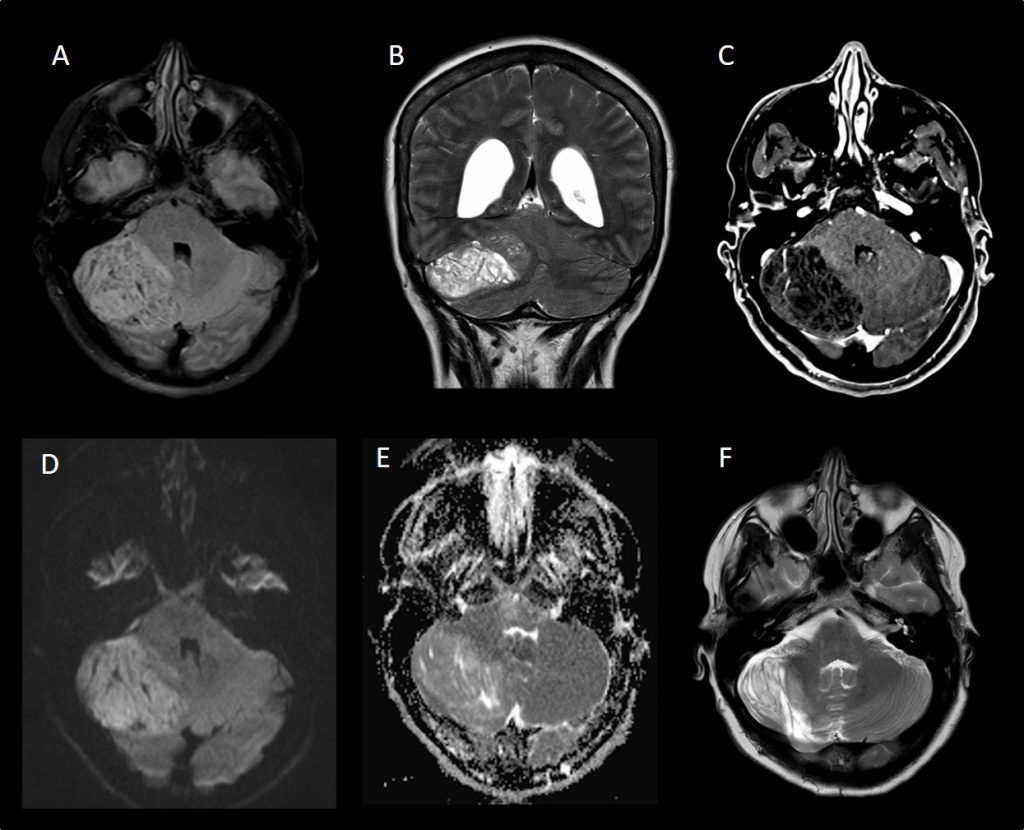

A: FLAIR axial . B: T2 coronal C: T1 con contraste. D: Difusión. E: Mapa de ADC. Se observa lesión expansiva y compresiva cerebelosa derecha, heterogénea con área lineales de hiper/hipointensidad, sin realce tras la administración de contraste, excepto algún vaso y con escasa restricción de la difusión. F: T2 axial post-quirúrgico.»

- El gangliocitoma displásico cerebeloso o enfermedad de LD es un proceso expansivo de la fosa posterior, unilateral y de lento crecimiento. Clínicamente se hace evidente durante la 2.a y la 3.a década de la vida, no muestra predilección por género y puede estar asociado a diversas anomalías del desarrollo. Las evidencias clínicas y su estrecha vinculación con la EC (complejo hamartoma-neoplasia múltiple) hablan a favor de un origen hamartomatoso. La RM es el método de elección para el diagnóstico, revelando una masa cerebelosa sin realce con el contraste, hipointensa en en T1 e hiperintensa en T2, con un patrón estriado de líneas paralelas en su superficie (también descrito como atigrado, característico de la lesión) compatible con engrosamientos foliares con estructuras venosas entre ellos.